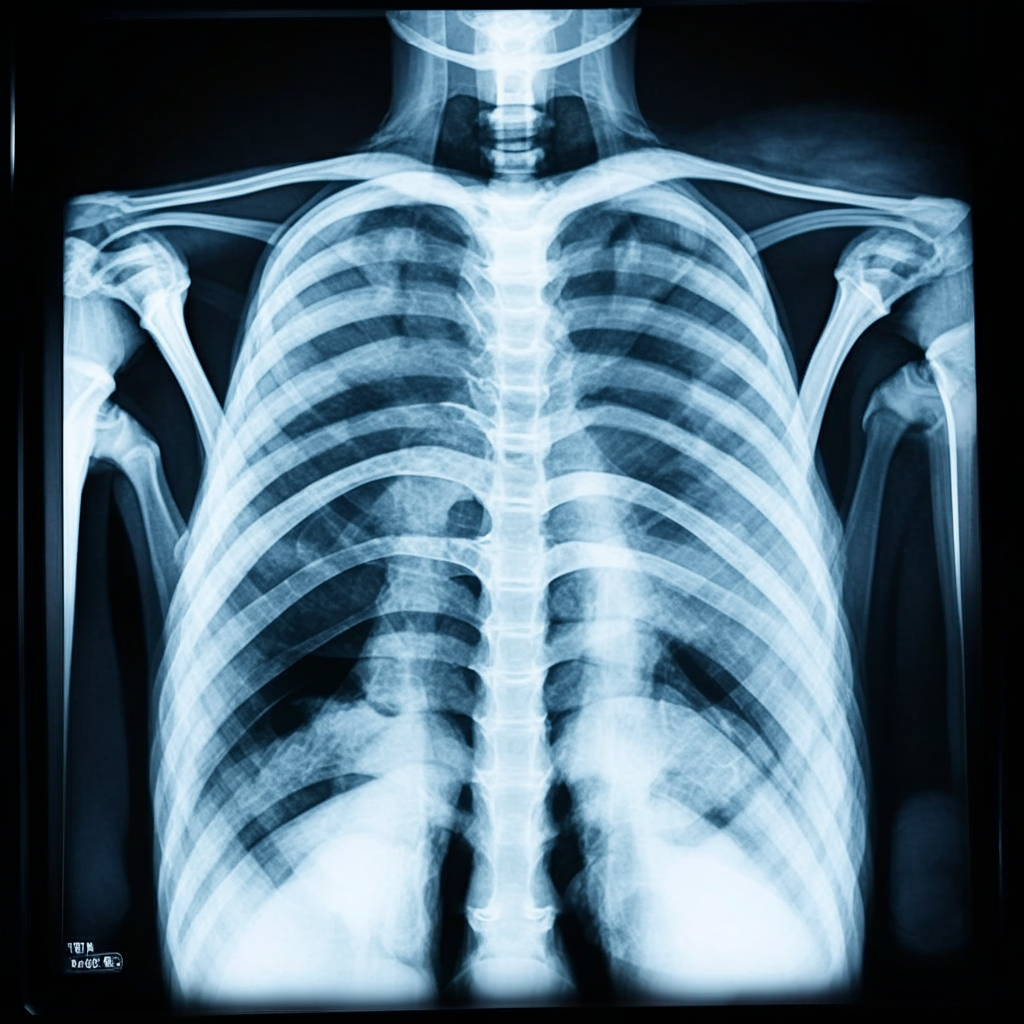

В рамках обследования проводится рентгенография (или флюорография) органов грудной клетки, а также соответствующие лабораторные анализы. В случае обнаружения признаков активного туберкулеза медицинская организация в обязательном порядке передает сведения в территориальный орган Роспотребнадзора, который и является тем самым органом по вынесению решения о нежелательности пребывания иностранных граждан в России.

После завершения лечения наш клиент получил медицинскую справку, в которой подробно указывались все аспекты его терапии: пройденный курс лечения, применяемые лекарства и, что особенно важно, заключение о том, что он не представляет опасности для окружающих. Этот документ стал ключевым элементом в нашем дальнейшей работе – вы можете увидеть его на фотографии.